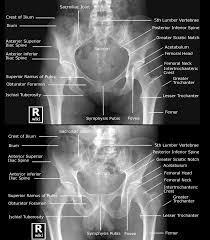

The pelvic spine is the posterior portion of the pelvis below the lumbar spine, composed of the sacrum and coccyx. Über 7 millionen englischsprachige bücher. See more ideas about pelvic floor, pelvic floor muscles, anatomy. The pelvis of males and females differ for obvious reasons. The bony framework of the pelvis is called the pelvic girdle. Anatomy of the male and female pelvis. Axial slice of the male pelvis with prostate, urinary bladder, muscles, bones and fossa. In general, the bones of the male pelvis are thicker and heavier, adapted for support of the male's heavier physical build and stronger muscles.

There are many organs that sit in the pelvis, including much of the urinary system, and lots of the male or female reproductive systems. Evolutionary scientists believe this stems from man's hunter roots, as a leaner pelvis made running easier. Human male anatomy, 3/4 figure muscular and skeletal systems, front view. The gonadal vessels refer to the testicular artery and testicular vein in males and the ovarian artery and ovarian vein in females. The floor of the pelvis is made up of the muscles of the pelvis, which support its contents and maintain urinary and faecal continence. The pelvic outlet is larger in females, which is necessary for childbirth. Anatomy of the human pelvis male vs female pelvis. The pelvic girdle consists of two symmetrical halves. The pelvic girdle, also known as the hip bone, is composed of three fused bones: Anatomy of the male pelvis on mr imaging: Male pelvic floor anatomy an understanding of pelvic floor anatomy is essential for interpreting imaging examinations of the pelvic floor, particularly in male patients, given the less common incidence of these examinations at most centers. Anatomy of the pelvic floor the male pelvic floor is a complex structure consisting of muscles, fasciae and ligaments that support the visceral organs. Line 2, which marks the pelvic outlet, travels from the coccyx to the lower border of the pubic symphysis.

The right gonadal vein drains into the inferior vena cava (ivc), and. Anatomy of the human pelvis male vs female pelvis. The anatomy of the pelvis varies depending on whether you are male or female. Evolutionary scientists believe this stems from man's hunter roots, as a leaner pelvis made running easier. Axial slice of the male pelvis with prostate, urinary bladder, muscles, bones and fossa. The pelvis of males and females differ for obvious reasons. Male false and true pelvis. Ƒ organs and structures of the female pelvis.

Pelvic bones are held together by the two main joints of the pelvis; The pelvic girdle consists of two symmetrical halves. Male pelvic floor anatomy an understanding of pelvic floor anatomy is essential for interpreting imaging examinations of the pelvic floor, particularly in male patients, given the less common incidence of these examinations at most centers. Anatomy of the pelvic floor the male pelvic floor is a complex structure consisting of muscles, fasciae and ligaments that support the visceral organs. It is located in the superficial perineal pouch of the pelvic floor, and is not visible externally. The skin, tissues and organs in the pelvis are supplied by the. There are many organs that sit in the pelvis, including much of the urinary system, and lots of the male or female reproductive systems. The male pelvis anatomy model is shown in median section. The male pelvic floor is a complex structure made up of muscles, ligaments, nerves and fascia. This short lecture from overcome pelvic pain for men explains male pelvic floor and bony pelvis anatomy. It is composed of the two hip bones and the sacrum. In general, the bones of the male pelvis are thicker and heavier, adapted for support of the male's heavier physical build and stronger muscles. The male pelvis tends to be slimmer, with a smaller inner area.